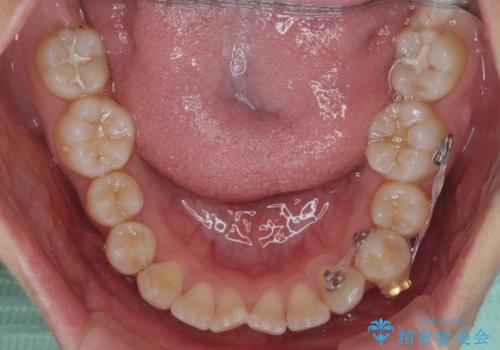

- 前歯のがたつきを気にして来院。

左下の小臼歯が捻転し、反対咬合になっていました。

先にワイヤーで部分矯正を行ってから、インビザラインの部分矯正を行いました。

先に難しい部分をワイヤー矯正することで、インビザラインの部分矯正コースで短期間で予算も抑えて確実に治すことができます。

専門的な話になりますが、下顎の小臼歯は円柱状の形をしており、インビザライン単独では捻転はほぼ治りません。

今回は左下の小臼歯が捻転が強く、そこが反対咬合になっていたため事前に部分矯正を行いました。